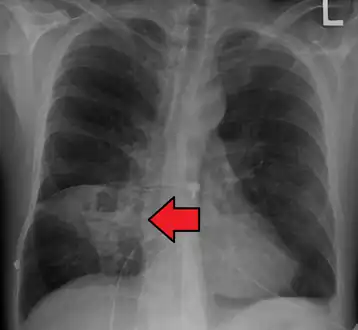

a,b)Hollow lesion in the lower left lung field was diagnosed as a lung abscess

Pulmonary abscess on CXR